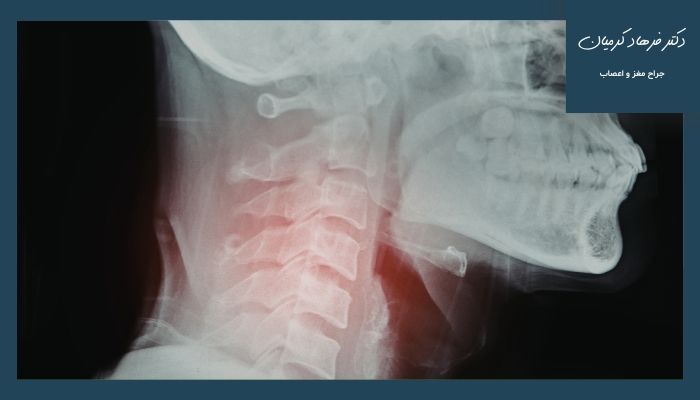

دیسک گردن و نشانههای خطرناک آن

دیسک گردن به بالشتکهای نرم و انعطافپذیری گفته میشود که بین مهرههای گردن قرار دارند و وظیفهشان جذب فشار و کمک به حرکت روان گردن است. وقتی به دلایلی مثل افزایش سن، نشستنهای طولانیمدت، کار با موبایل و کامپیوتر، وضعیت بد بدن، ضربه یا بلند کردن اجسام سنگین این دیسکها دچار فرسایش یا بیرونزدگی میشوند و به اعصاب اطراف فشار وارد میکنند و مشکل دیسک گردن ایجاد میشود. در بسیاری از افراد این مشکل در ابتدا خفیف است؛ اما اگر بهموقع تشخیص داده نشود میتواند شدیدتر شود.